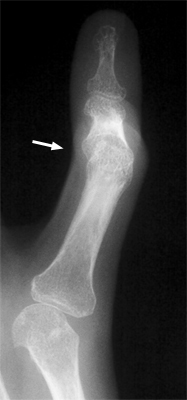

Boutonniere Deformity

Rheumatoid arthritis

Among the many osseous abnormalities that may be seen in Rheumatoid Arthritis, the boutonniere deformity is the culmination of multiple abnormalities in the hand. Specifically, the deformity arises from hyperextension of the distal interphalangeal joint, while the proximal interphalangeal joint is flexed.